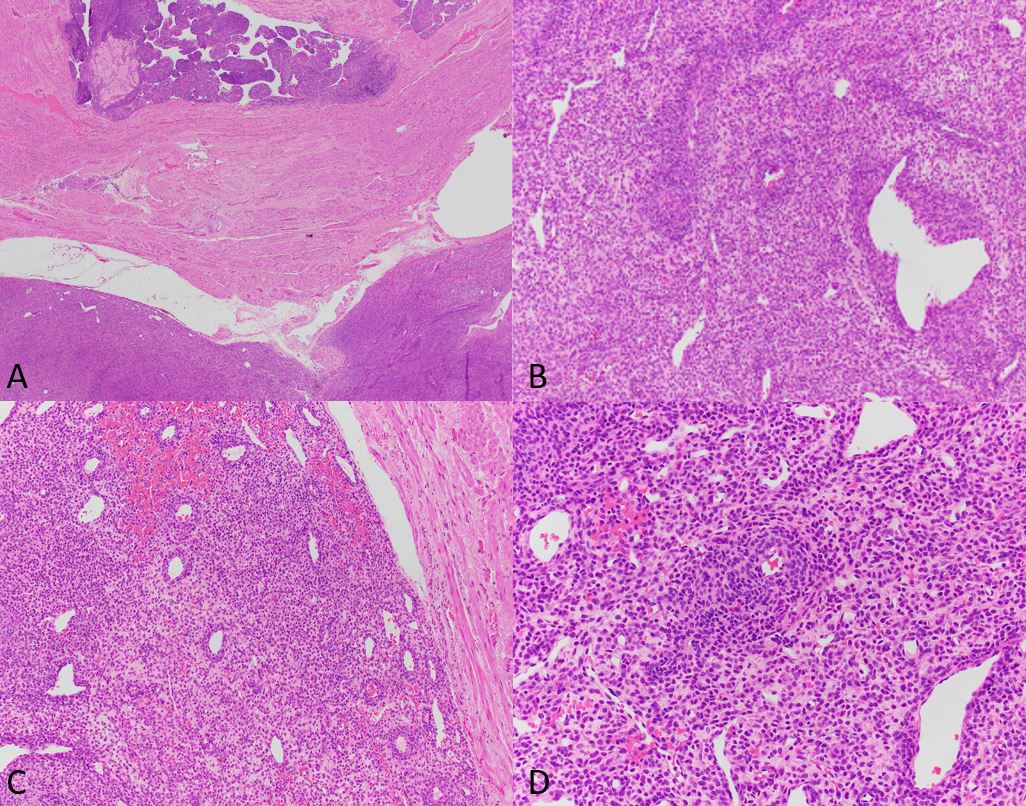

Histologically, they can be well circumscribed or infiltrative, with a ‘tongue-like’ appearance. Variable epithelioid cells, arranged in nests or diffuse sheets, to spindled cells, arranged in short fascicles, may be present. A delicate vascular network is typical and tumor cells often cluster around these vessels. Cytoplasm is eosinophilic to granular. So-called “spider cells”, formed when cells have central eosinophilic cytoplasm surrounded by a peripheral clear zone, may be present.

Criteria proposed for assessing malignant potential are tumor size > 5cm, high nuclear grade and cellularity, readily identifiable mitotic figures, infiltrative growth, necrosis and vascular invasion. Tumors with 2 or more of these high-risk features are considered malignant. Tumors 5 cm or more in size with no other high-risk features, or tumors with nuclear pleomorphism only, are considered of uncertain malignant potential. Tumors <5 cm with <2 high risk features are considered likely benign. When malignant, behavior is like a sarcoma with metastasis to lungs, liver, etc.